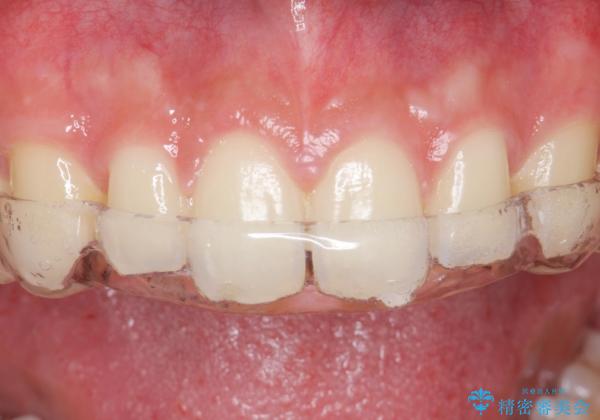

ナイトガードで歯ぎしり予防

しっかりしたナイトガードが欲しいとの事だったので自費のナイトガードのご案内をしました。

- 自費ナイトガード 3.3万円費用は治療当時の料金となります

ナイトガードは夜寝ている時、無意識に歯ぎしりをして歯がすり減ることを防ぐことがあります。また、歯が割れたり欠けたりするのも防いでくれます。